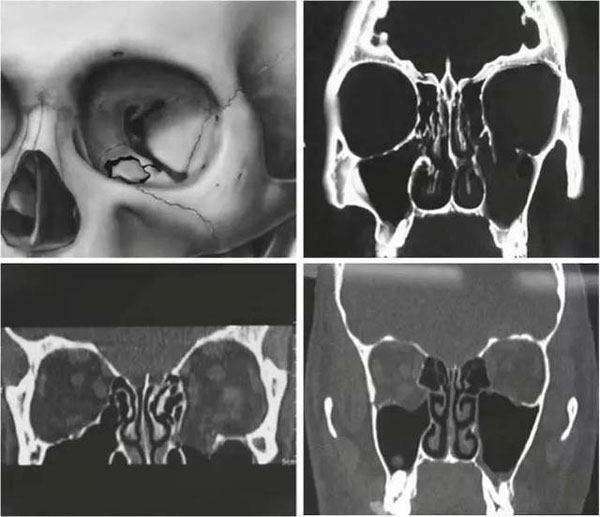

因為是對顱骨組織的修補,選擇材料的標準是很高的。首先要求有很高的生物相容性,并且需要同時保證一定的強度和剛度,既提供足夠堅強的保護,也要滿足術中塑形的需要,達到外形修復整容滿意的效果。目前很多醫院臨床上常用鈦合金網作為顱骨修補材料,那么顱骨修復鈦合金網硬度一般多大呢?很遺憾,鈦網的硬度不是很高,臨床上也經常出現鈦網修補后受外力變形的案例。除此之外,鈦網還有其他諸多弊端,比如術后感染、排異、材料外露、慢性疼痛、冷熱敏感、影響CT核磁等檢查等等問題。所以鈦合金網并不是顱骨修復的理想材料。

目前臨床開始應用一種新型的顱骨修補材料——聚醚醚酮,也就是PEEK材料,取得了很好的臨床效果。PEEK材料是一種特種高分子材料,其生物相容性好,力學性能優異,防護性強,術后舒適度高,逐漸為神經外科醫師和顱骨缺損患者所青睞。